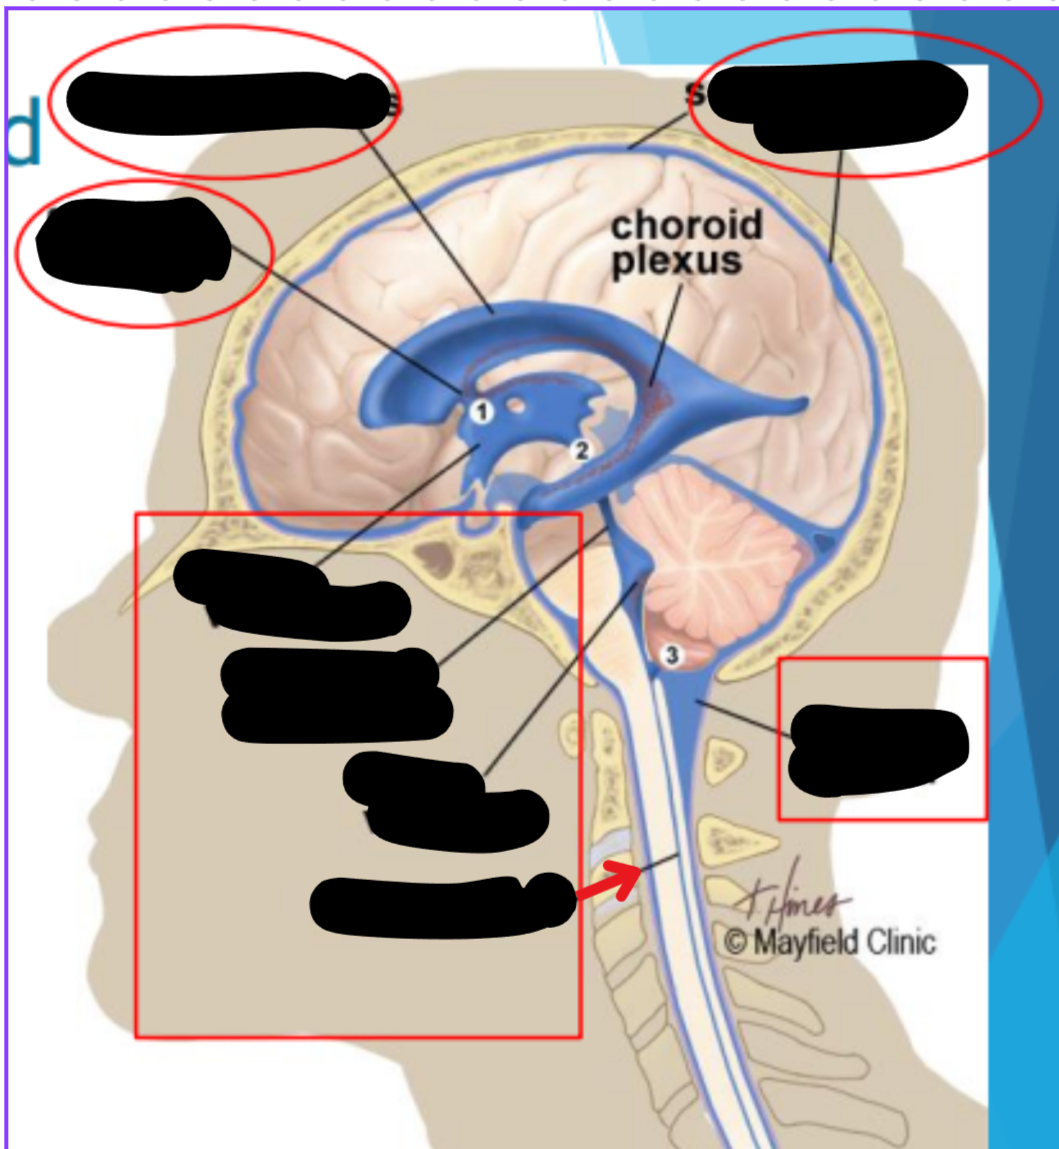

Ventricles

The ventricles contain the choroid plexus which creates CSF

Choroid plexus

Produces cerebrospinal fluid (CSF)

Maintains pressure in the brain

Cushions brain to prevent injury

Ventricular system

Two lateral ventricles

Foramen of Monro

Third ventricle

Aqueduct of Sylvius

Lateral Horns

Central horn (connects inside spinal cord)

Fourth ventricle

Cycle of CSF

Places where CSF flow can become obstructed

Obex